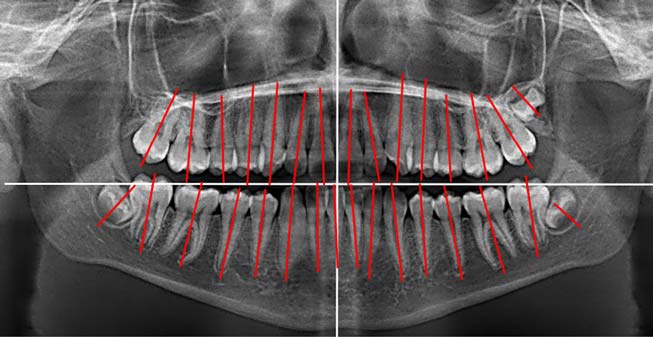

На ортопантомограмме направление прорезывания зачатков постоянных зубов было нарушено, выявлен недостаток места в дуге для прорезывания боковых резцов (рис. 2).

Рис. 2. Ортопантомограмма пациента Л., возраст 8 лет 6 мес

В возрасте 12 лет по причине задержки прорезывания постоянных зубов и неравномерной резорбции корней временных моляров [28] пациент был направлен на ортопантомографию и удаление временных зубов (рис. 3).

Рис. 3. Ортопантомограмма пациента Л. 12 лет

Кроме того, на ортопантомограмме выявили искривление корней постоянных зубов (рис. 7), что затрудняло их перемещение, а нормализация наклона корней при этом не представлялась возможной.

Рис. 7. Ортопантомограмма пациента Л. 15 лет

На ортопантомограмме после завершения ортодонтической коррекции окклюзии выявлены незначительная асимметрия положения зубов и искривление корней отдельных зубов (рис. 9).

Рис. 9. Ортопантомограмма пациента Л. 17 лет